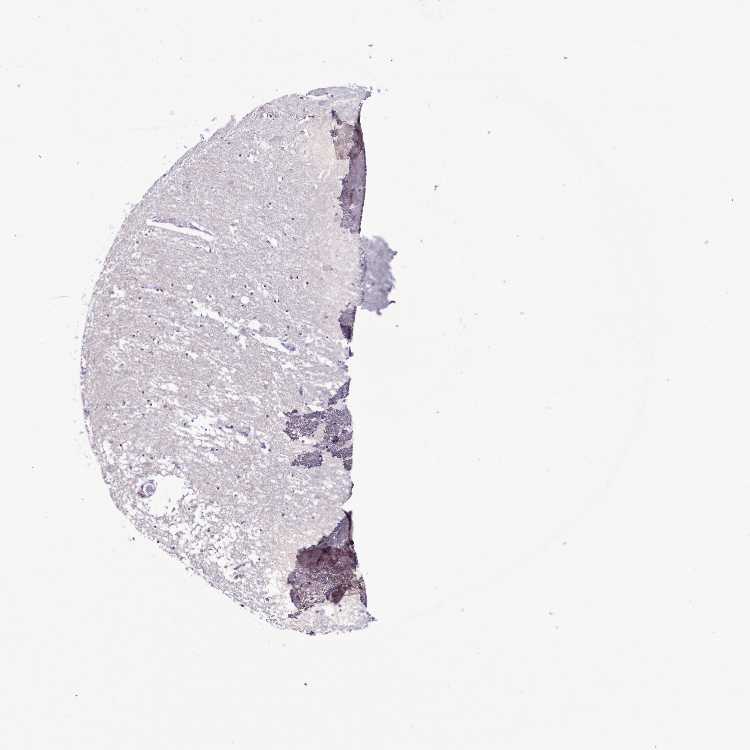

HIPPOCAMPUS - Antibody stainingi

Antibody staining in the annotated cell types in the current human tissue is reported as not detected, low, medium, or high, based on conventional immunohistochemistry profiling in selected tissues. This score is based on the combination of the staining intensity and fraction of stained cells.

Each image is clickable and will lead to virtual microscopy that enables deeper exploration of all samples and also displays staining intensity scores, fraction scores and subcellular localization as well as patient and tissue information for each sample.

Antibody HPA038862

Neuronal cells Not detected